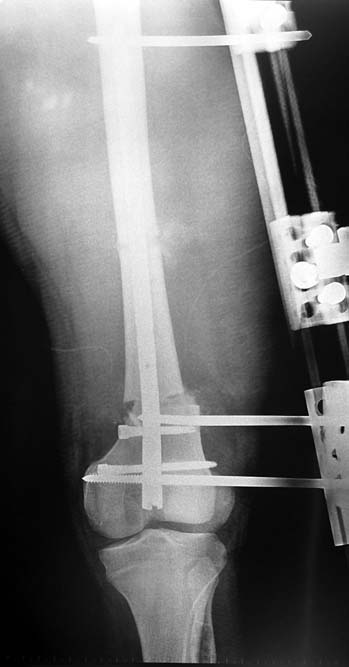

Bu Bacak Kısalık tipi bir kırığın kısalmış pozisyonda kaynaması ile oluşur. Bir çok vaka yetişkinlerde görülür ve sadece bir uzatma ile tedavi edilebilir. Ek deformiteler de aynı anda düzeltilebilir. Bu hastaların çoğu çivi üzerinden uzatma veya tam implante edilen çivi ile tedavi edilebilirler.